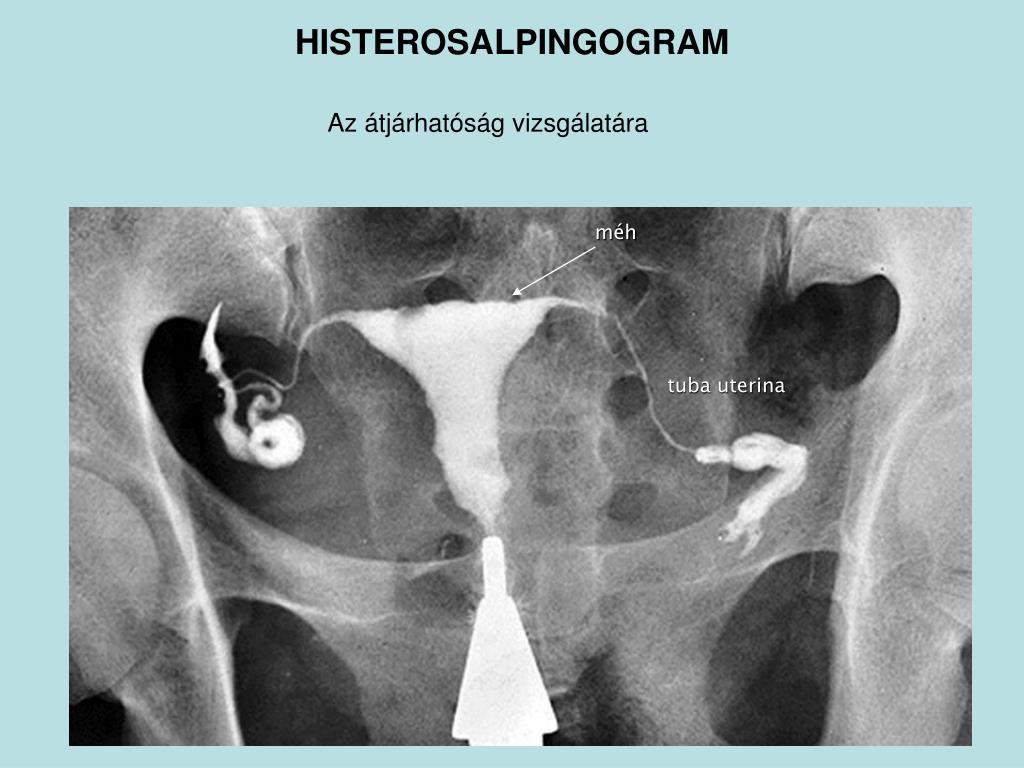

Гистеросальпингография: описание и фотографии